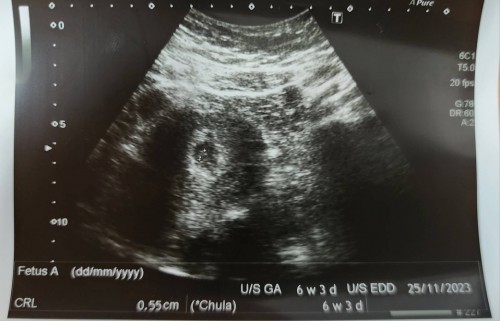

ตอนนี้ได้ 6week 5วันค่ะ ซาวน์แล้วเจอหัวใจกระพิบๆสีแดงๆในจอของหมอค่ะ แต่ยังไม่ได้ฟังเสียงหัวใจค่ะ แบบนี้เราดีใจได้แล้วใช่ไหมคะ หรือรอลุ้นให้อายุครรภ์มากขึ้นกว่านี้เพื่อให้ชัดเจน

แบบนี้ก็ชัดแล้วค่ะ ยินดีด้วยนะคะ รอบหน้าซาวด์จะพอเห็นเป็นตัวแล้ว